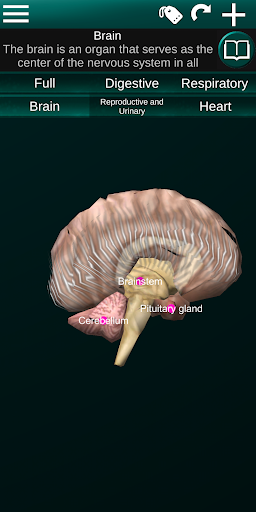

Показує 3D анатомічну модель основні органи людського тіла та опис кожного з них.

* Мозок, який включає головний мозок, мозочок і стовбур мозку.

* Легкий доступ і навігація (масштабування, 3D-обертання).

* Описи кожного органу.